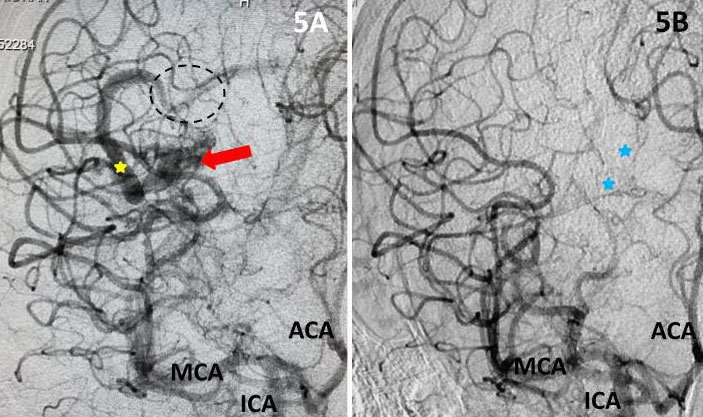

Fig 2. AP view, mid-arterial phase of a right internal carotid artery (ICA) injection. The large tortuous draining vein (yellow star) with the suggestion of clot (dotted circle) can be seen. AVM nidus (red arrow), MCA (middle cerebral artery, ACA (anterior cerebral artery).

The patient was taken to the angio-suite where an angiogram confirmed a high flow, high pressure AVM fed primarily by the posterior cerebral artery with a small collateral from the middle cerebral artery (Fig 2 and 3). The AVM drained into a tortuous, partially occluded and stenotic single draining vein.